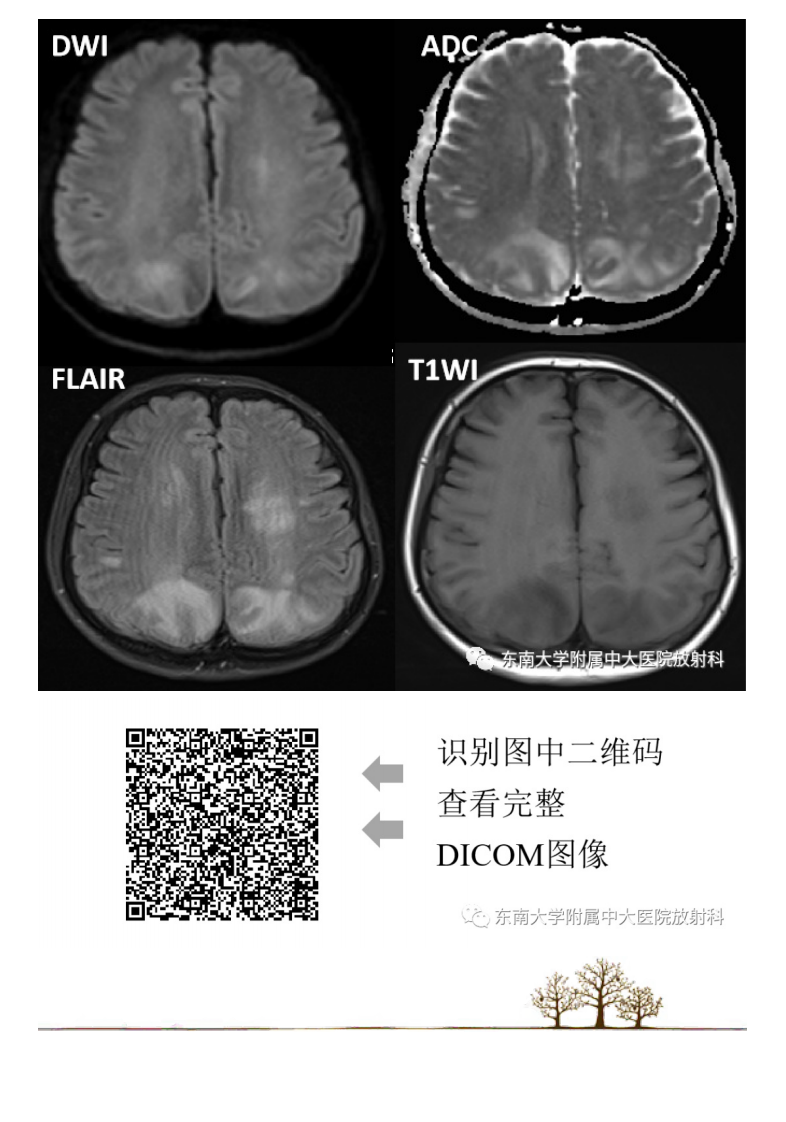

20210415_2【晨读结果公布】2021.04.14神经系统疾病——可逆性后部脑病综合征(PRES).pdf